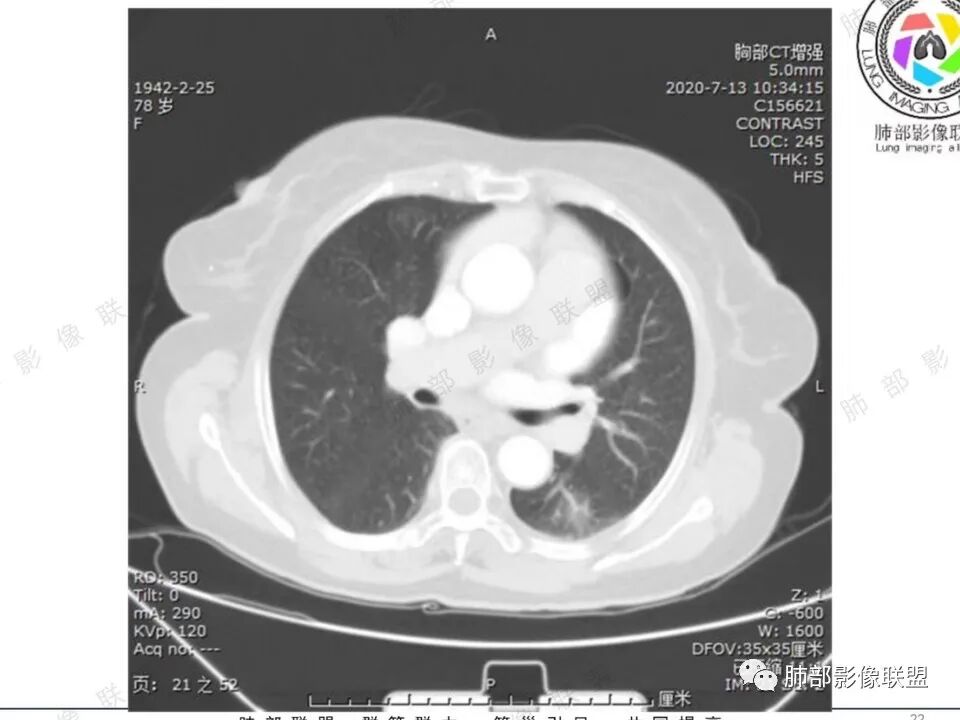

穿越七海的风: 右肺下叶不规则结节伴空洞,似鬼脸,壁厚度不均,壁内结节,首先考虑恶性,既往甲状腺癌病史,不除外转移。

蔡笑燕: 右肺不规则实性囊腔结节,囊腔内有血管走形和分隔,有分叶,细短毛刺,周围有清晰磨玻璃,胸膜牵拉,考虑IAC。

看图说话: 不规则结节,假大空,壁结节,边缘收缩,胸膜牵拉,周围有分叶,毛刺,伴有清晰磨玻璃影,周围有小结节,考虑肺腺癌,鉴别:1:结核,2,隐球菌。

哦落花时节 (刘朋): 中青年男性,右肺下叶不规则结节,内见多发囊腔,囊腔内壁不光滑,邻近叶间裂明显局部凹陷,有胸膜牵拉,血管聚集,考虑囊腔性腺癌,鉴别转移。

清茶: 青年男性,右肺下叶高密度结节影,有毛刺、分叶,内见空洞,边界尚清,考虑恶性,腺癌可能。

王秀仙: 右下肺 囊腔性结节,囊壁不均匀增厚,壁结节,毛刺分叶,胸膜凹陷,周边有边界清楚磨玻璃影,考虑囊腔型肺癌,腺癌。

心灵鸡汤: 青年男性,有甲状腺癌穿刺活检病史, 右肺下叶不规则囊腔,内壁不光整,似见壁结节,偏远侧见实性结节,病灶边缘可见分叶,毛刺,邻近血管支气管走行不自然,邻近斜裂牵拉,考虑二元,恶性结节,腺癌可能性大,转移、结核待排。